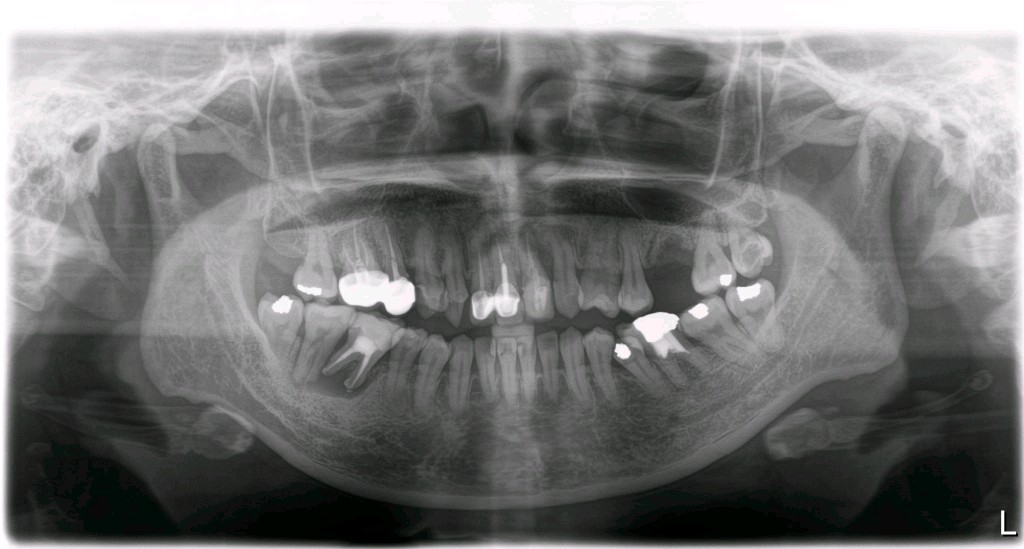

患者女,三十岁,11、12、21牙已行根管治疗,11、21烤瓷全冠修复。由于长时间烤瓷牙的佩戴,导致牙龈边缘发黑,颈缘处牙龈组织出现"黑线"。腭侧部分也出现了崩瓷的现象。对于这种情况,建议患者尽早重新修复,避免二次伤害。患者最终选择重新修复,也给出患者合理的方案,患者选全瓷冠修复,与今日佩戴完毕。边缘密合度良好,形态色泽自然美观,患者满意。

术中